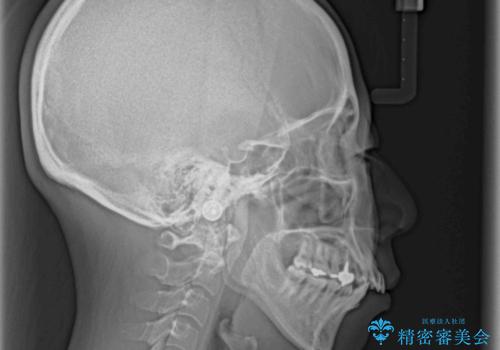

- 出っ歯と口の閉じにくさ、デコボコを気にして来院された患者様です。

口元の突出感を改善するため、上下左右第一小臼歯4本の抜歯を行い、ワイヤー装置による矯正治療を行うこととしました。

上下前歯の距離が大きかったため、上下の歯が接触するまでに時間がかかりました。